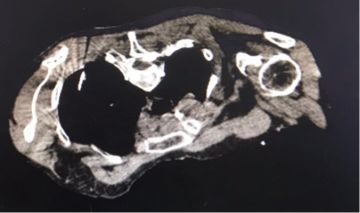

混合性磨玻璃結(jié)節(jié)影密度低,縱隔窗不顯影,穿刺定位是在肺窗下,縱隔窗僅見穿刺針。